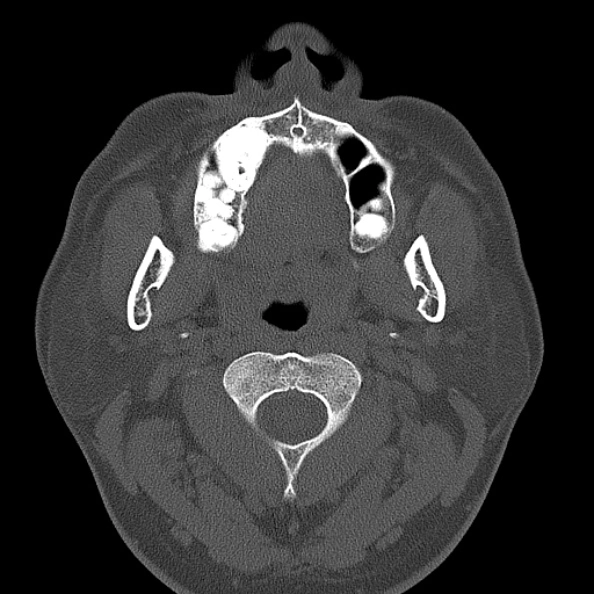

U men răng (Ameloblastomas)